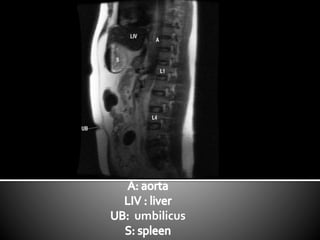

This document lists anatomical structures in the human abdomen including the umbilicus, aorta, skin, subcutaneous fat, sigmoid colon, erector spinae muscles, transverse colon, urinary bladder, right lobe of liver, gall bladder, and pancreas.